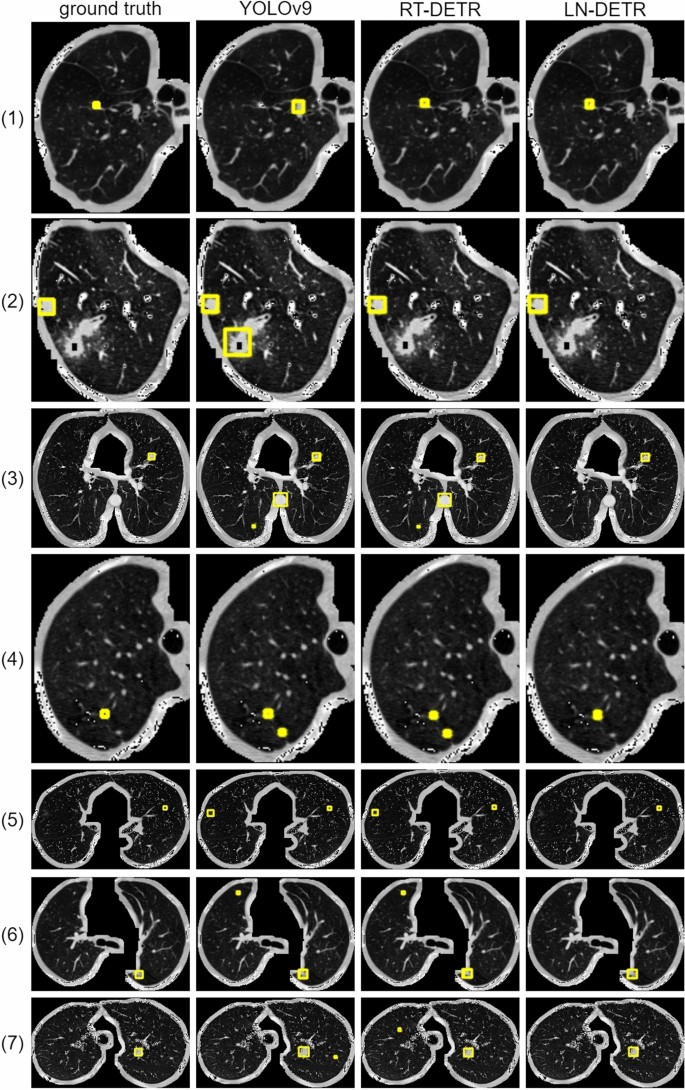

Figure 7 shows a comparison of the detection results on the LUNA16 dataset between multiple models and LN-DETR. Due to the small size of the targets, for easier observation, the images have been cropped. YOLOv9, as a general-purpose object detection model, exhibits insufficient adaptability in its anchor box design and feature pyramid structure for small targets such as pulmonary nodules (3-30 mm in size). Pulmonary nodules in CT images are characterized by low contrast and diverse appearances, and the single-stage detection architecture of the YOLO series tends to suffer from missed detections due to inadequate granularity in feature extraction. While RT-DETR achieves real-time performance by compressing computational overhead, this comes at the cost of sacrificing the ability to perform refined multi-scale feature fusion. It can be observed that the baseline model RT-DETR and YOLOv9, encountered issues such as missed detections, false positives, and lower accuracy during the lung nodule detection process, as they were not specifically optimized for lung nodule detection. Furthermore, the results of LN-DETR demonstrate that the proposed DSDF and JCF modules optimize the model’s feature fusion and downsampling architecture, significantly enhancing its detection sensitivity to pulmonary nodules. As a result, LN-DETR demonstrates excellent detection performance for lung nodules, outperforming other models in terms of both false positive rate and detection accuracy.

Visualization of experimental results of three methods. Labels represent the ground truth, LN-DETR represents our method.